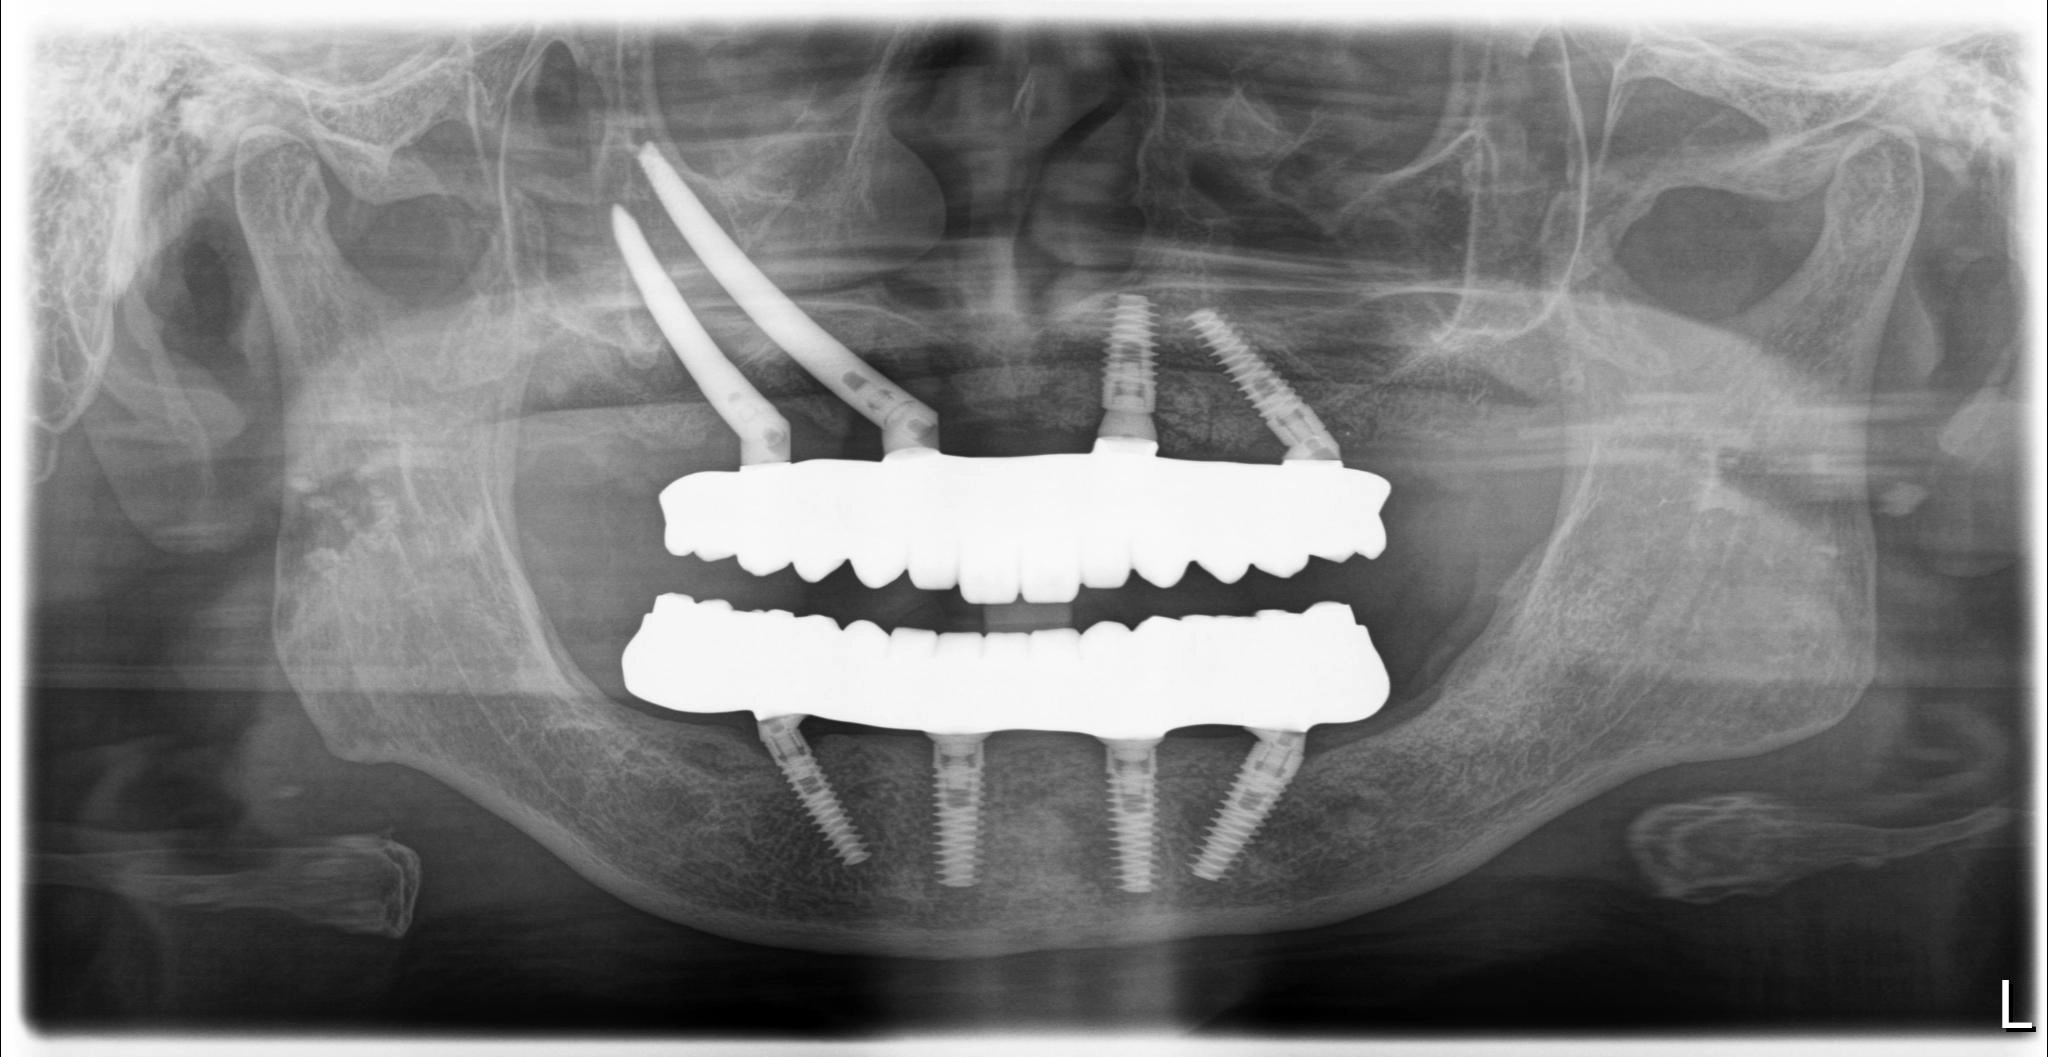

術前

術後

内容 :上下顎オールオン4ザイゴマ2

費用 :5,552,800円

※モニター価格

期間 :半年

リスク:出血・腫れ・痺れ・痛み